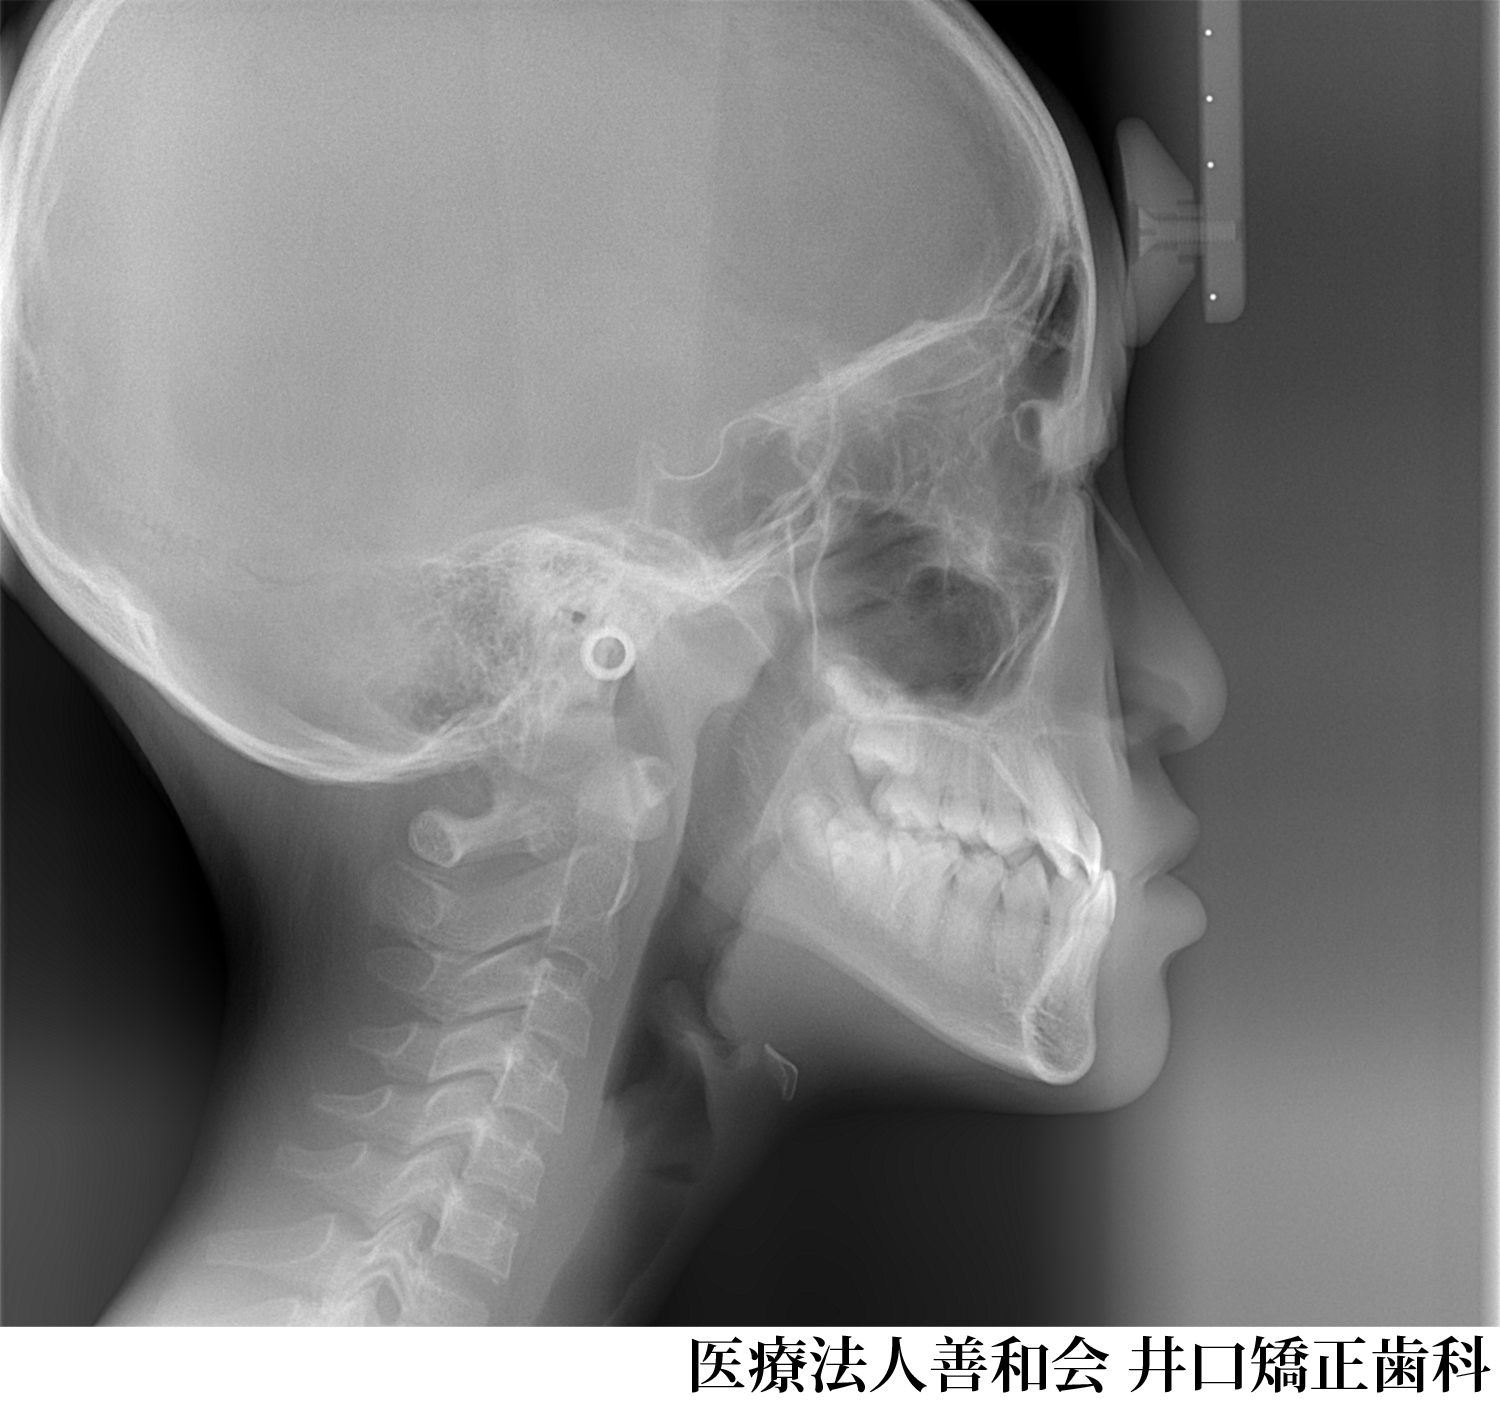

¡Ú¾ÉÎã1¡Û¥Þ¥ë¥Á¥Ö¥é¥±¥Ã¥ÈË¡¤Ç¼£ÎŤò¹Ô¤Ã¤¿À®¿Í¶ºÀµ¤Î¾ÉÎã

- ¼£ÎÅÁ°

- ¼£ÎÅÃæ

- ¼£ÎŸå

- ¼£ÎÅ̾

- ¥Þ¥ë¥Á¥Ö¥é¥±¥Ã¥ÈË¡¤Ç¼£ÎŤò¹Ô¤Ã¤¿À®¿Í¶ºÀµ¤Î¾ÉÎã

- ½é¿Ç»þǯÎð:34ºÐ ½÷À

¼£ÎÅÆâÍÆ

´µ¼ÔÍͤξɾõ

Angle Iµé¡¢±±»õ¤Î³ú¤ß¹ç¤ï¤»¤ËÁ°¸åÊý¸þ¡¢Æâ³°¤ÎÊý¸þ¤Î³ú¤ß¹ç¤ï¤»¤Î¤º¤ì¤Ïǧ¤á¤Þ¤»¤ó¤Ç¤·¤¿¤¬¡¢Á°»õ¤Î¥¹¥Ú¡¼¥¹ÉÔÂ(Í𹺻õ)¤È±¦Â¦¤Î¦ÀÚ»õ¤Î¸òºµÒû¹ç(ËÜÍè¡¢¾å¤Î»õ¤¬³°Â¦¡¢²¼¤Î»õ¤¬Æâ¦¤Ë¤¢¤ë¤â¤Î¤¬¡¢µÕ¤Ë¤Ê¤Ã¤Æ¤¤¤ë¾õÂÖ)¤òǧ¤á¤Þ¤·¤¿¡£

¤Þ¤¿¡¢¾å¤Î¦ÀÚ»õ¤Ïâä¾®»õ¤È¤Ê¤Ã¤Æ¤¤¤Þ¤·¤¿¡£ -

¼£ÎÅË¡

¾å¤Î¦ÀÚ»õ¤¬âä¾®»õ¤Ç¡¢¥µ¥¤¥º¤¬¾®¤µ¤¤¤¿¤á¡¢¾å²¼¤ÎÁ°»õ¤Î¥µ¥¤¥º¥Ð¥é¥ó¥¹¤¬°¤¤¾õÂ֤Ǥ·¤¿¡£

¤½¤Î¤¿¤á¡¢º¸²¼¤ÎÁ°»õ1ËܤòÈ´»õ¤·¤Æ¡¢¥µ¥¤¥º¥Ð¥é¥ó¥¹¤òÀ°¤¨¤ë¤È¤È¤â¤Ë¡¢»õÊÂ¤Ó¤ÎÆÌ±ú¤ò¤Û¤°¤¹¤¿¤á¤Î¥¹¥Ú¡¼¥¹¤È¤·¤ÆÍøÍѤ·¤Þ¤·¤¿¡£

¥Þ¥ë¥Á¥Ö¥é¥±¥Ã¥ÈÁõÃÖ¤òÁõÃ夷¡¢ÇÓÎó¤ò¹Ô¤¤¤Þ¤·¤¿¡£ -

¼£ÎÅ·ë²Ì

¸òºµÒû¹ç¡¢ÁÑÀ¸¤Ï²þÁ±¤·¡¢¤¤ì¤¤¤ËÇÓÎ󤵤ì¤Þ¤·¤¿¡£